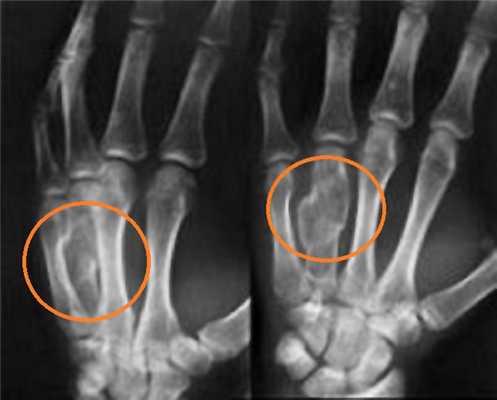

- Перелом Смита (сгибательный перелом). Причиной травмы служит падение на вытянутую руку, на ее тыльную сторону. Кость ломается и при этом происходит смещение костных отломков в сторону ладони.

- Перелом Коллеса (разгибательный перелом). Повреждение случается при падении человека на ладонь, наблюдается смещение костных отломков в сторону большого пальца и тыльной поверхности кисти.